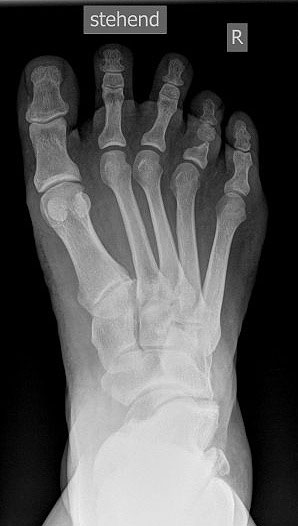

• Fuß belastet dp und seitlich (Abb. 14 und 15)

• Saltzman view (Abb. 16)

Zum Lesen der Bildbeschreibung und zur Vollansicht bitte die Bilder anklicken. Bilder: A. Simon

Typische Merkmale der Standard-dp-Röntgenaufnahme des Fußes im Stand

• Talus und Calcaneus verlaufen fast parallel

• Os naviculare ist gegenüber dem Talus nach medial gedrängt

• Metatarsalia überlappen sich basisnah

• Metatarsale I erscheint verkürzt

• Metatarsus adductus

Typische Merkmale der Standard-Seitaufnahme des Fußes im Stand